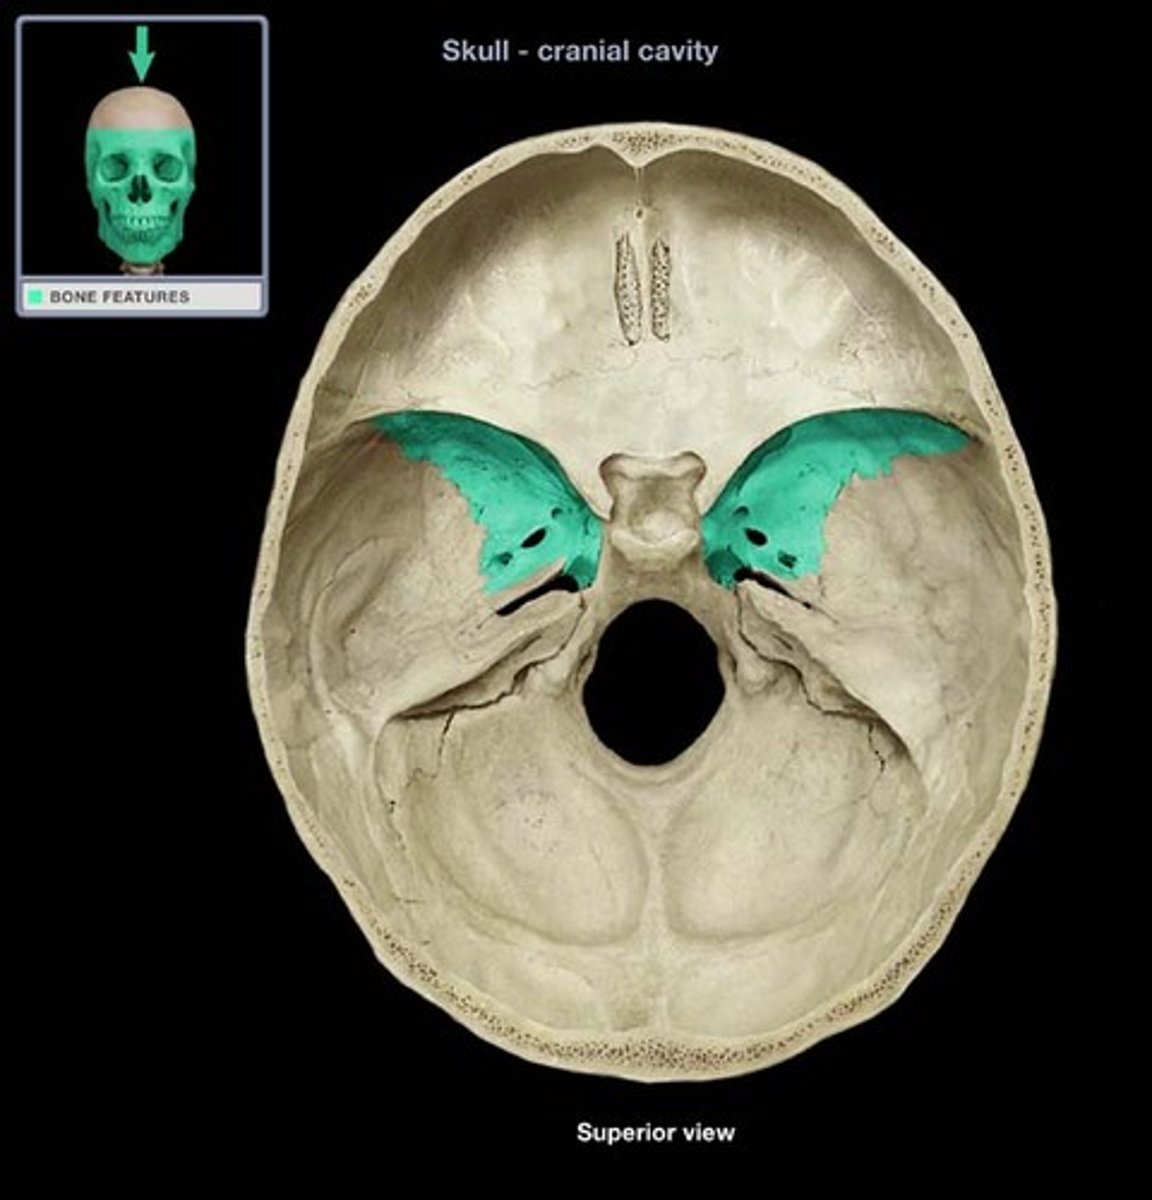

Sphenoid

Name the bone.

greater wings

Name this structure.

foramen ovale

Name this structure.

foramen rotundum

Name this structure.

foramen spinosum

Name this structure.